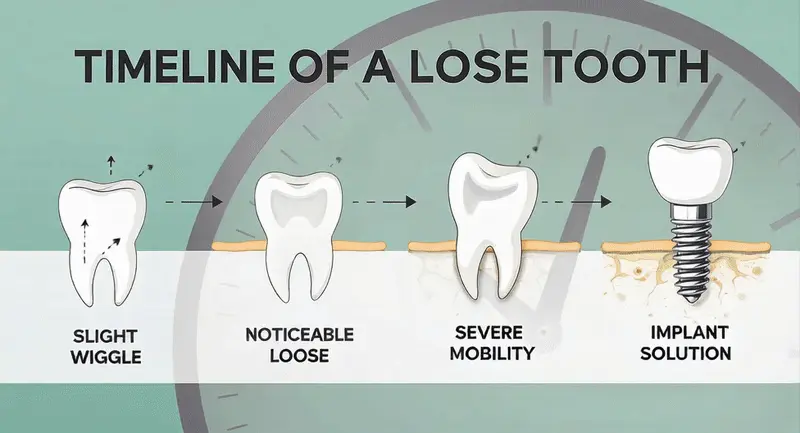

When you first notice a tooth feeling slightly loose, it’s easy to dismiss it as a minor concern. Perhaps you think it will tighten back up on its own, or maybe you’re hoping it’s just your imagination.

Unfortunately, loose teeth are rarely a temporary problem—they’re often the beginning of a journey that leads directly to dental implant treatment. Understanding this progression can help you make informed decisions about your oral health and potentially save you time, money, and discomfort down the road.

When this support system becomes compromised—whether through periodontal disease, trauma, or other factors—teeth begin to lose their stability. What starts as barely perceptible movement can quickly progress to noticeable looseness, and eventually, tooth loss becomes inevitable.

Once a tooth becomes loose, it sets off a cascade of problems that often makes implant treatment the most viable long-term solution. Here’s why:

Bone Loss Accelerates: When a tooth is loose, it’s no longer providing the normal stimulation that keeps the surrounding bone healthy and dense. This lack of stimulation causes the bone to begin resorbing (dissolving away), creating even less support for the tooth. It’s a vicious cycle that rarely reverses on its own.

Neighboring Teeth Suffer: A loose tooth can’t properly share the load during chewing, which means adjacent teeth must work harder. This increased stress can lead to additional tooth mobility, creating a domino effect throughout your mouth.

Bite Problems Develop: As loose teeth shift position, your bite becomes uneven. This can cause jaw pain, headaches, and additional stress on other teeth, potentially leading to more tooth loss.